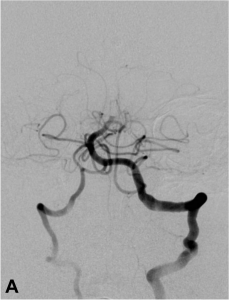

Exemple d’embolisation par coiling simple. A. Angiographie montrant l’anévrysme en position communicante

postérieure. B. Mise en place du microcathéter dans l’anévrysme. C. Résultat après le déploiement des coils ;

occlusion complète de l’anévrysme.